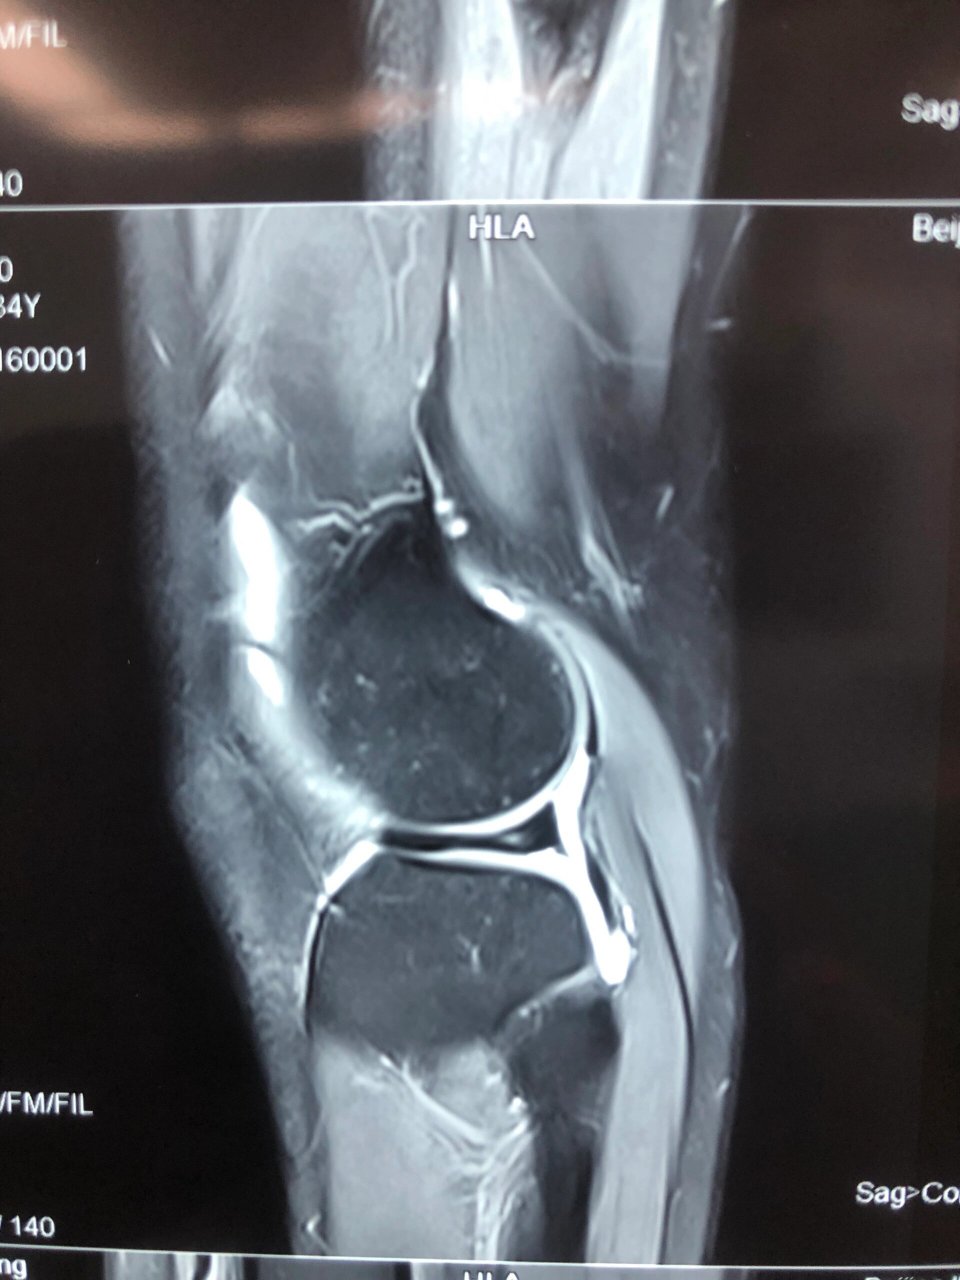

核磁共振 显示半月板三度损伤 去了四家一线城市三甲医院 骨科 - 抖音

图片尺寸1440x1920